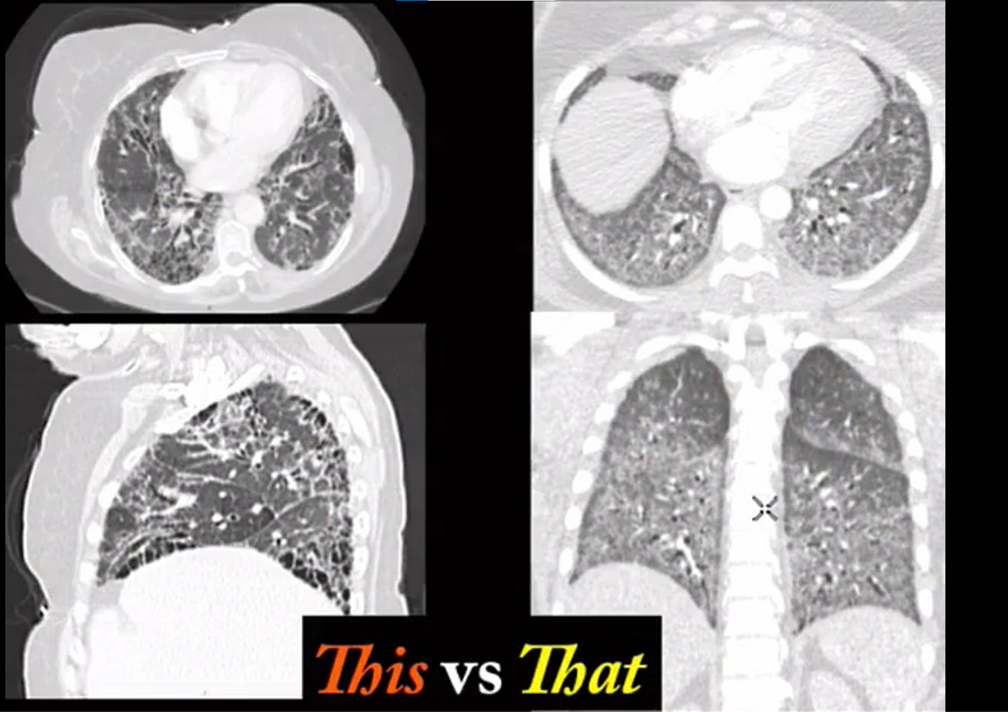

uip distribution

worse in lower lobes

lung disorder with sparing of the costophrenic angles